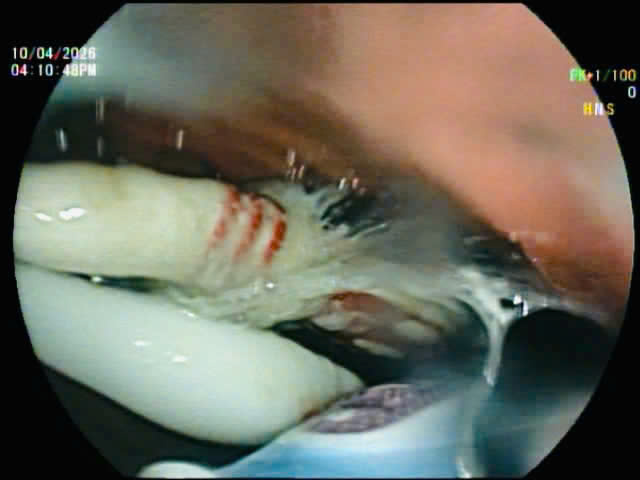

Hình ảnh 3 chiếc bàn chải đánh răng trong đường tiêu hoá của bệnh nhân qua hình ảnh nội soi.

Các bác sĩ nội soi gắp các bàn chải đánh răng ra khỏi đường tiêu hoá.